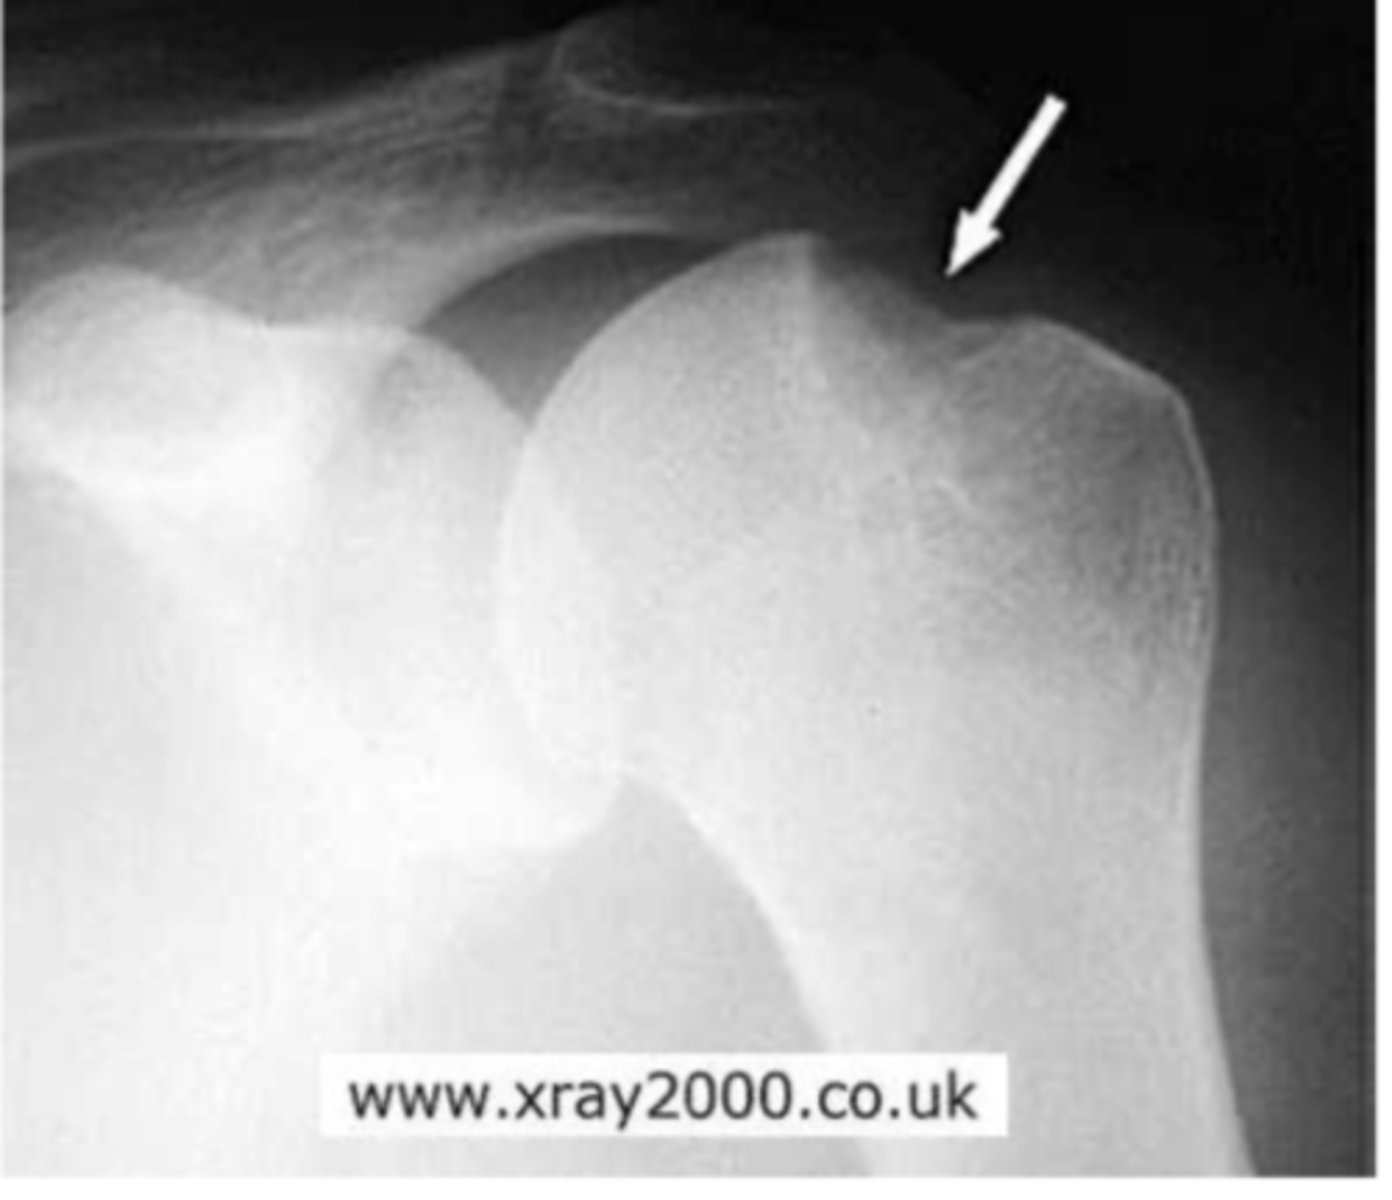

Hill Sachs lesion

What is the issue?

Bankart fracture